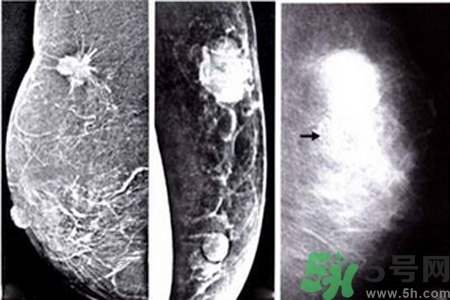

乳腺增生鈣化是乳腺癌常見(jiàn)的影像學(xué)表現(xiàn)之一。某些特異形態(tài)的乳腺增生鈣化是乳腺癌的危險(xiǎn)因素,統(tǒng)計(jì)資料表明65%的乳腺癌有鈣化,其中70%為惡性鈣化。

早期乳腺癌唯一的X線征象

成簇樣微小鈣化常是早期乳腺癌唯一的X線征象。根據(jù)微小鈣化形態(tài)、大小、數(shù)量和密集度等表現(xiàn)可反映病變性質(zhì)和范圍。微小鈣化點(diǎn)可位于腫塊內(nèi)或周圍,總數(shù)目6~15枚,密度不均,大小不等。

乳腺X線檢查可提高隱匿癌、微小癌(直徑小于10mm)和早期癌的診斷率。直徑小于10mm腫塊定性困難,但細(xì)沙型鈣化常是惡性病變的警報(bào);若同時(shí)出現(xiàn)周圍結(jié)構(gòu)紊亂,雙側(cè)不對(duì)稱,血管影增粗等征象則惡性病變可能性更大。